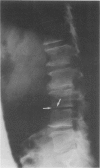

A patient with osteomyelitis of the spine complicating bacterial endocarditis due to Streptococcus milleri is discussed. To our knowledge, this is the first time this organism has been associated with this complication.